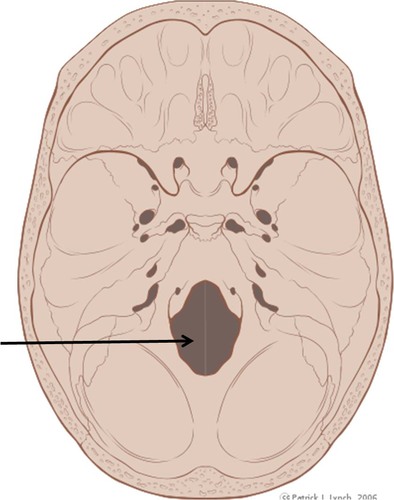

crista galli

cribriform plate

greater wing of sphenoid

lesser wing of sphenoid

sella turcica